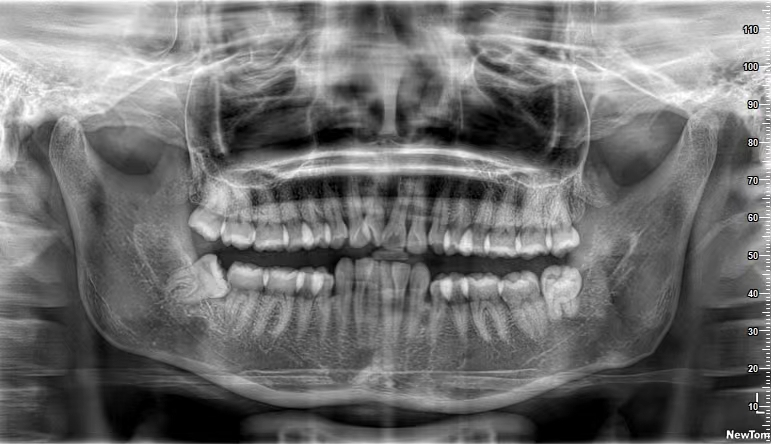

口腔曲面断层篇(全景片)

通过X线球管与胶片匣相对弧形运动,将上下颌骨的结构展示为连续的平面影像。常用于观察恒牙、乳牙龋坏情况;下颌神经管、上颌窦、上下颌骨囊肿,外伤,炎症等情况及其与周围组织的关系。

恒牙期曲面断层片